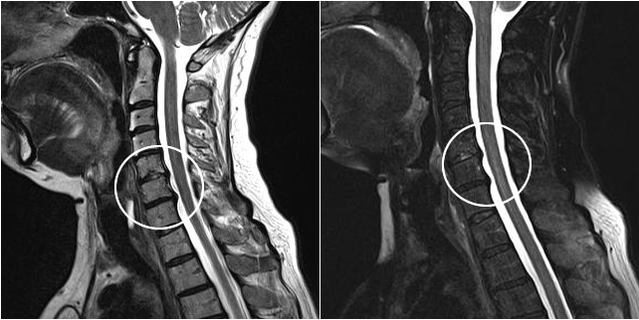

Sodobne diagnostične metode vključujejo MRI in CT, ki omogočajo najbolj natančno preučevanje procesov uničenja hrustanca in kostnega tkiva. Prav tako je s to tehniko priročno diagnosticirati kile in druge okvare mehkih tkiv v bližini vira bolezni.

Cervikalna osteohondroza na MRI sliki